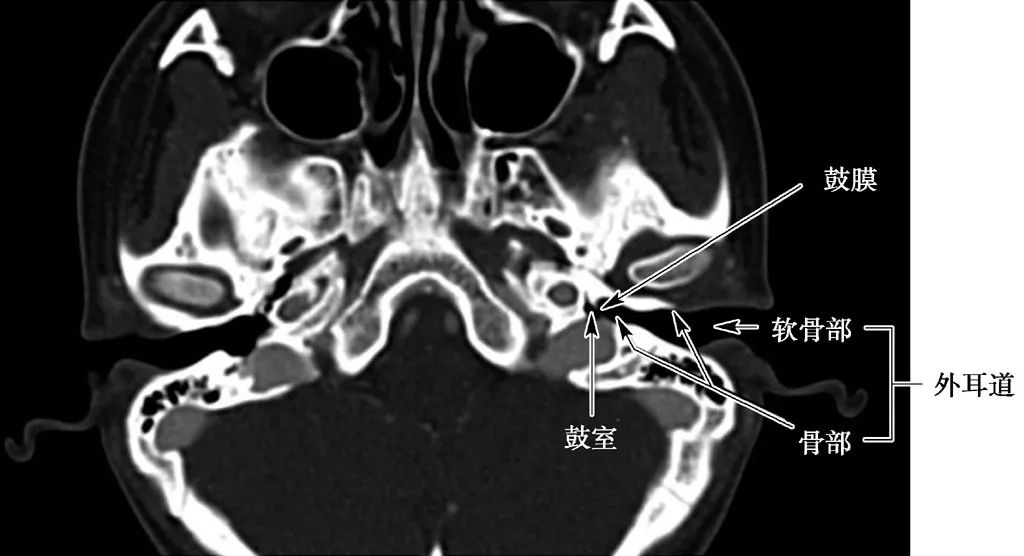

外耳道结构

(CT横断面)

中耳结构

(CT横断面自下至上两个层面)